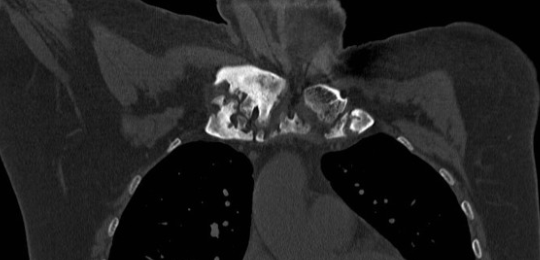

Sterno-claviculaire

• Synovite

• Ostéocondensation

e07e285f1afae487afa2733fbb744f1a.png

d04653affe524ca33dc0be438e387c63.png